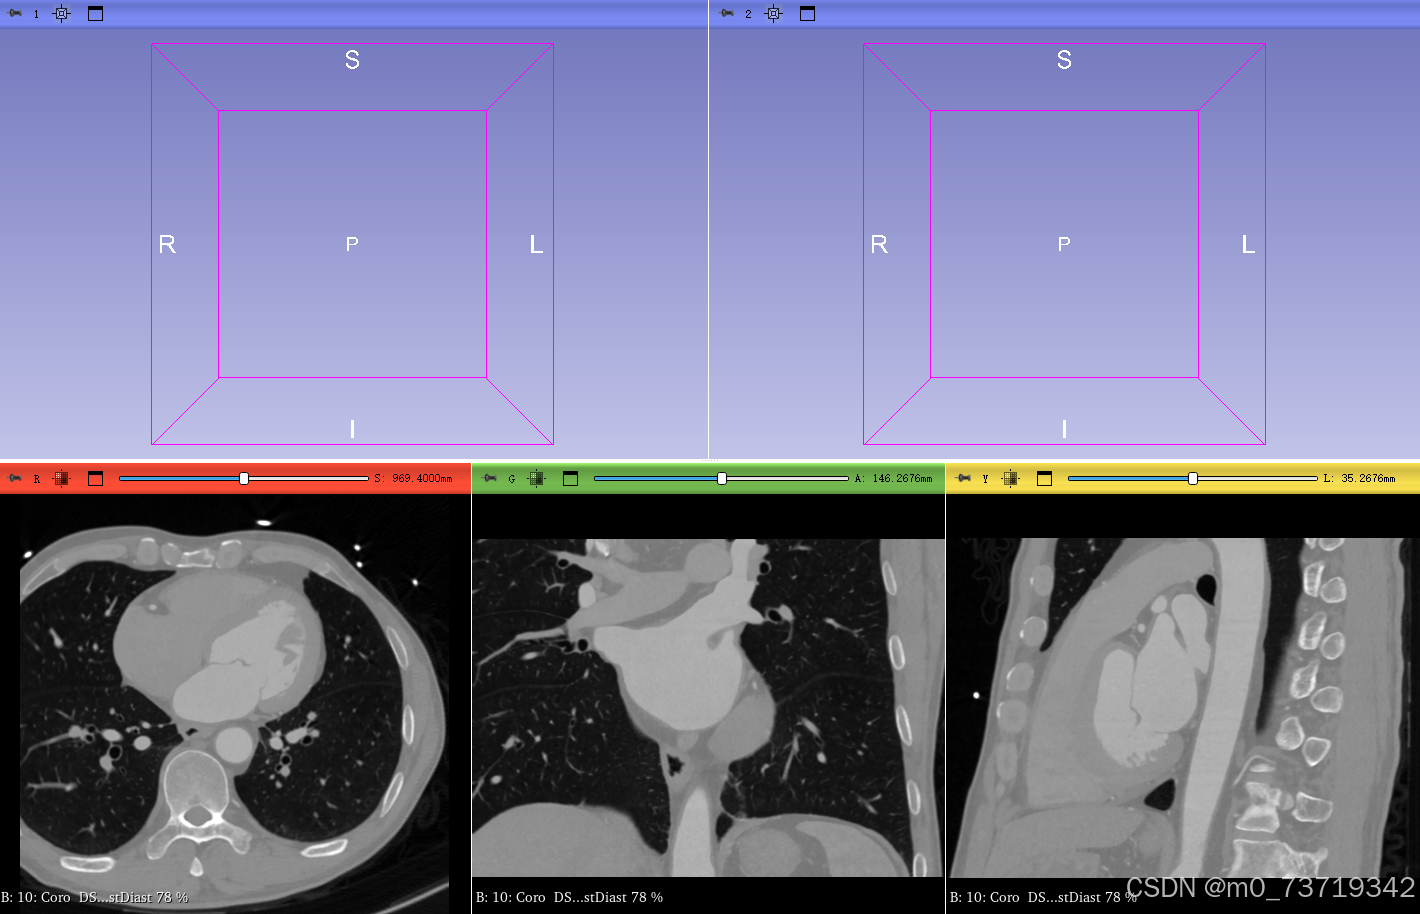

选择病人所有dicom图像(全选快捷键CTRL+A)导入得到如下视图

问题:无法显示五个视图

解决方法:点击如下按钮选择Dual 3D选项